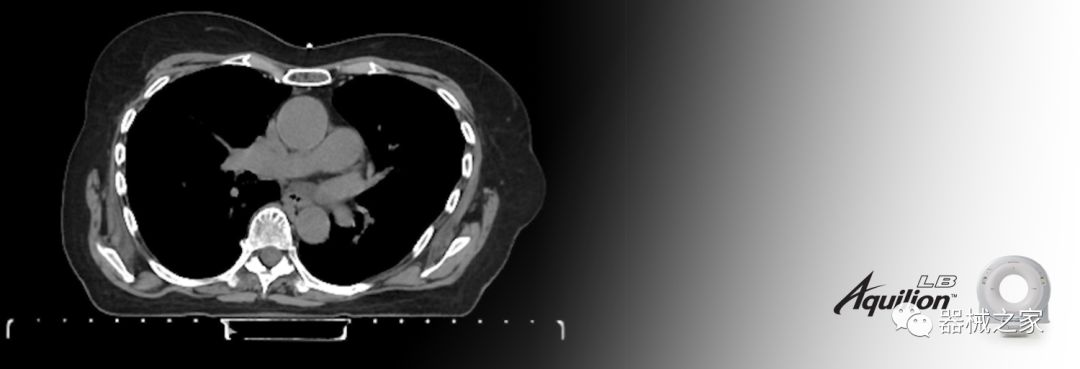

佳能醫(yī)療的Aquilion Lightning 80掃描儀還以緊湊,經(jīng)濟(jì)的包裝提供高質(zhì)量的成像。Aquilion Lightning 80旨在可靠,高效地運(yùn)行,在繁忙的環(huán)境中生成高質(zhì)量的圖像。

Aquilion LB專為滿足腫瘤學(xué)挑戰(zhàn)而設(shè)計(jì),同時(shí)優(yōu)先考慮患者護(hù)理。Aquilion LB的內(nèi)徑為90 cm,能夠幫助復(fù)雜的患者設(shè)置并提高患者的舒適度。CT模擬定位可以輕松鏡像放射治療定位,更加自信。該系統(tǒng)采用0.5 mm x 16排(32層)PUREViSION探測(cè)器技術(shù),70 cm視野,AIDR 3D和SEMAR技術(shù)。